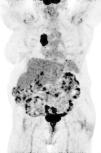

Radiología (English Edition) European Diploma in Radiology (EDiR) clinical cases

Case for diagnosis

European Diploma in Radiology (EDiR) clinical cases